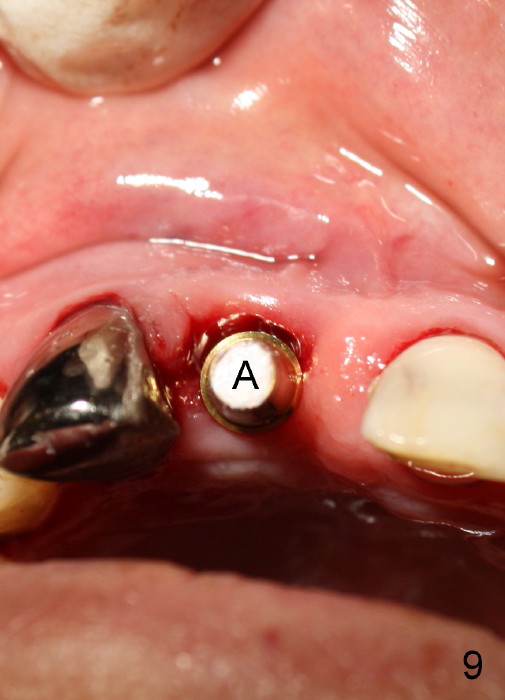

A 64-year-old lady requests replacing #7 and 8 crowns (Fig.1,2). When #8 is extracted, the labial plate is found to be missing (Fig.3). Following 2 mm pilot drill (Fig.4,5 P), 3.8 mm tap drill (Fig.6,7 T) and 4.5x14 mm implant (Fig.8 I) and 4.8 mm abutment (Fig.9 A), corticocancellous bone is harvested from the left tuberosity and placed in the labial gap of the socket (Fig.10 G). Collagen dressing is placed over the bone graft (Fig.11 C). The former is secured in place by an immediate provisional (P).

The patient returns for follow up 8 days postop and the labial margin of the provisional looks long. The metal crown is changed to a provisional at the visit. Eight days later, the provisional at the site of #8 is removed for labial margin trimming; the labial gingiva heals (Fig.14 *). The labial plate remains slightly convex (Fig.15). The labial margin of the provisional at the site of #8 is at the same level of that of #9.